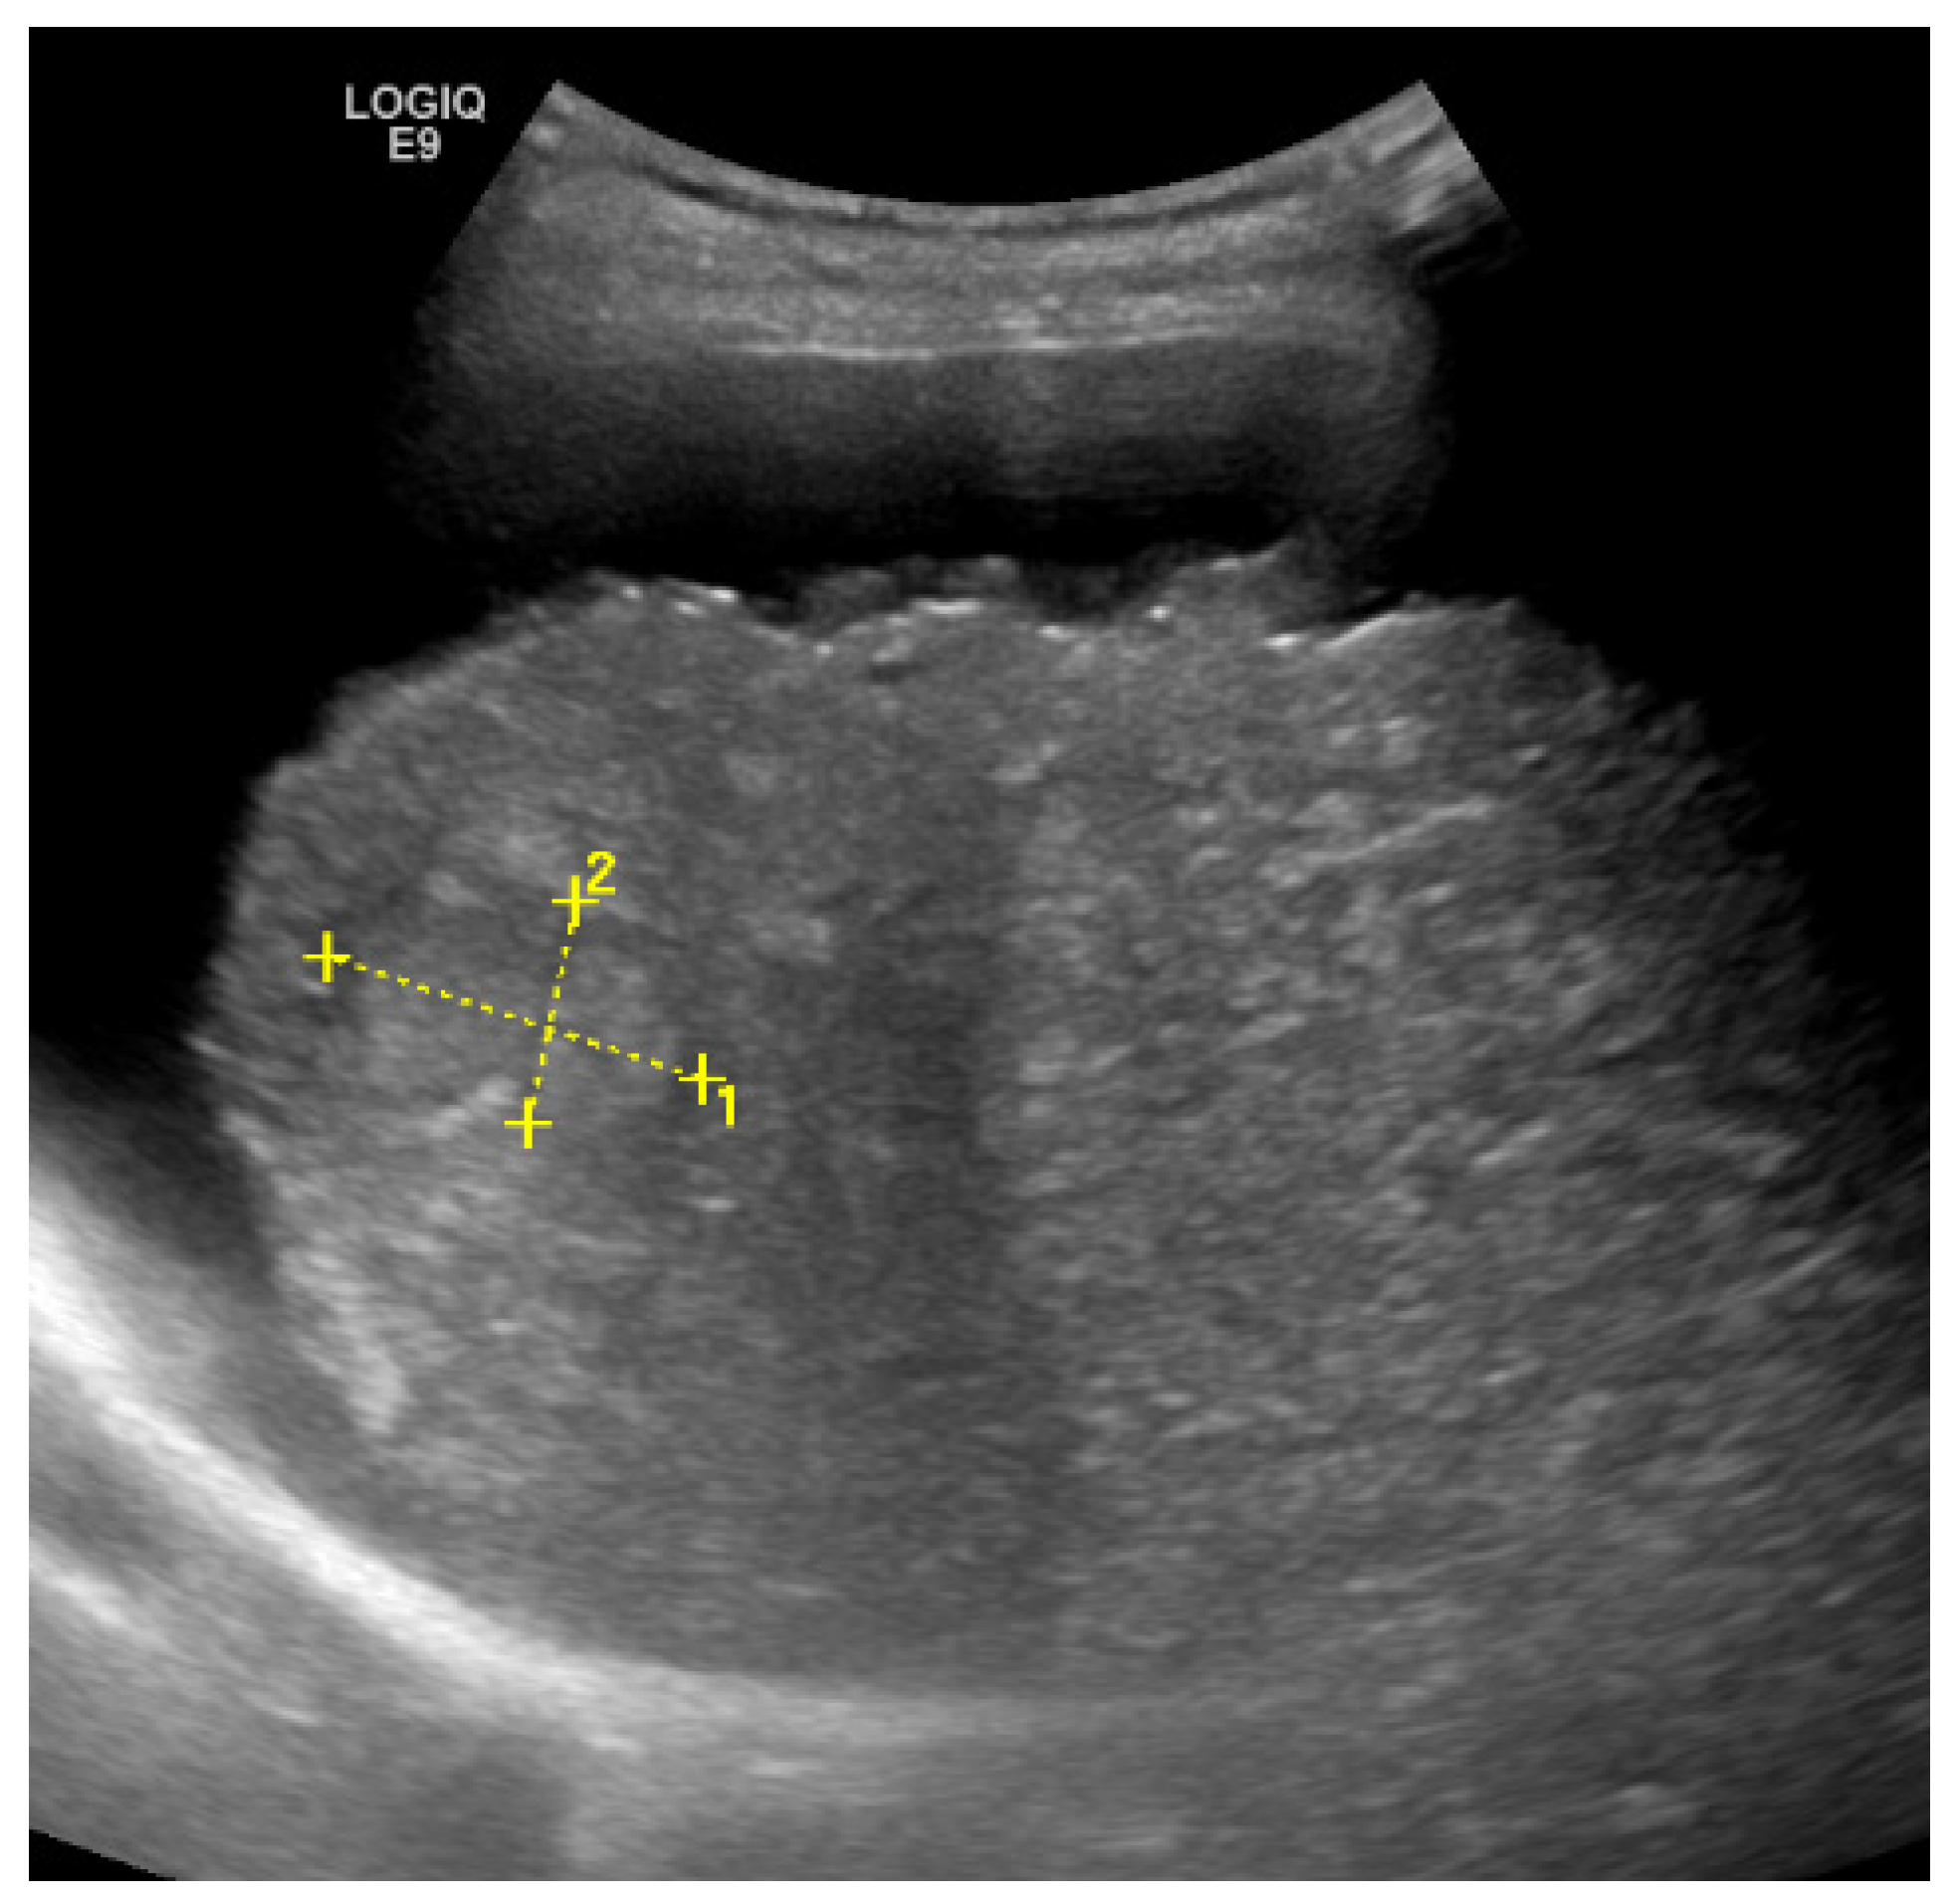

3. Liver Fibrosis

Elastography